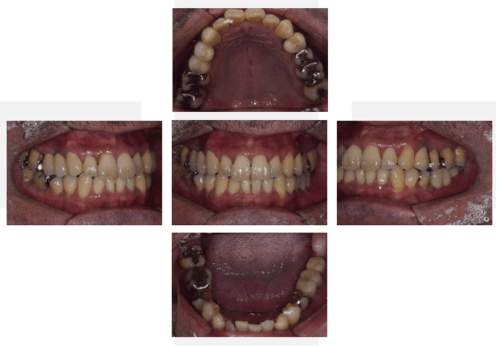

口腔内写真

- Befor

- After

| 年齢 | 50代・男性 |

|---|---|

| 主訴 | 左上7番 左下5番7番 |

| 治療内容 | ・インプラント埋入 ※1:GBR(骨造成)・・・骨再生誘導法。骨の高さや厚みを人工骨や人工膜などを使用し再生する方法 |

| 治療費 | 合計:1,809,500円(税込) ■内訳 ・左上7番 ・左下5番7番 |

| 治療期間 | 左上7番約1年 左下5番7番約10ヵ月 |

| 治療方針 | 左上7番は昔他院で被せものをしており、被せものの中が歯ぐきの中まで虫歯になっていたため抜歯せざるを得ない状態だった。抜歯と同時に骨造成を行い、骨が出来るまで4ヵ月待ってからインプラントを埋入した。 ※2ポンティック・・・歯のない部分を補うダミーの歯。 |

| 担当者所見 | 元々金属の被せものが多く入っていたため、2次カリエス※3が多かった。今回は金属ではなく、ジルコニアを使用し、2次カリエスにならないよう、患者様にはブラッシング指導とメンテナンスの重要性をお伝えした。 ※3二次カリエス・・・詰め物や被せものを入れた歯が虫歯になること。 |